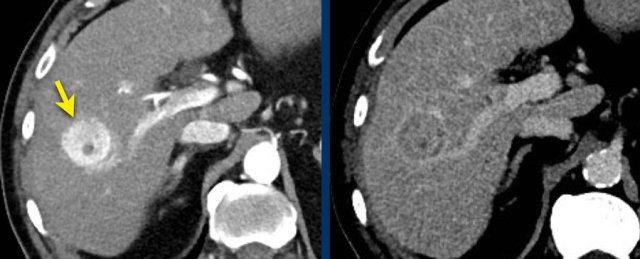

The images show an only mild rim-like arterially enhancing lesion in segment V with washout.

A linear area of hypoenhancement is seen extending from the mass which is suspicious of tumor in vein (yellow arrow).

Since we are not absolutely sure that it is a tumor thrombus, we cannot categorize this as LR-TIV.

A follow up CT was done, showing severe progression of the tumor as well as vascular involvement of the anterior right portal vein (white arrow).

Now we are sure of tumor invasion in the portal vein.